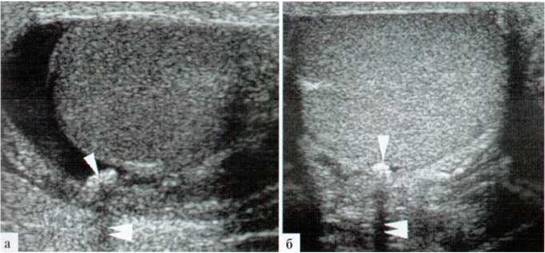

В редких случаях на фоне водянки оболочек яичка удается визуализировать неизмененную гидатиду (рис. 1.3).

Рис. 1.3. Неизмененная гидатида яичка (стрелка) на фоне водянки оболочек яичка, сосудистый рисунок в ней при ДДС (б) не прослеживается

Визуализируется неизмененная гидатида как овальной формы образование, фиксированное к придатку иди яичку, размеры ее обычно в пределах 2x3 мм. Сосудистый рисунок даже в относительно крупной неизмененной гидатите зафиксировать не удается. Структура ее гомогенная, средней эхогенности, изоэхогенна паренхиме яичка (рис. 1.4).

Рис.1.4. Относительно крупная (2x3мм) неизмененная гидатида яичка (стрелка), сосудистый рисунок в ней при ДДС (б) не прослеживается